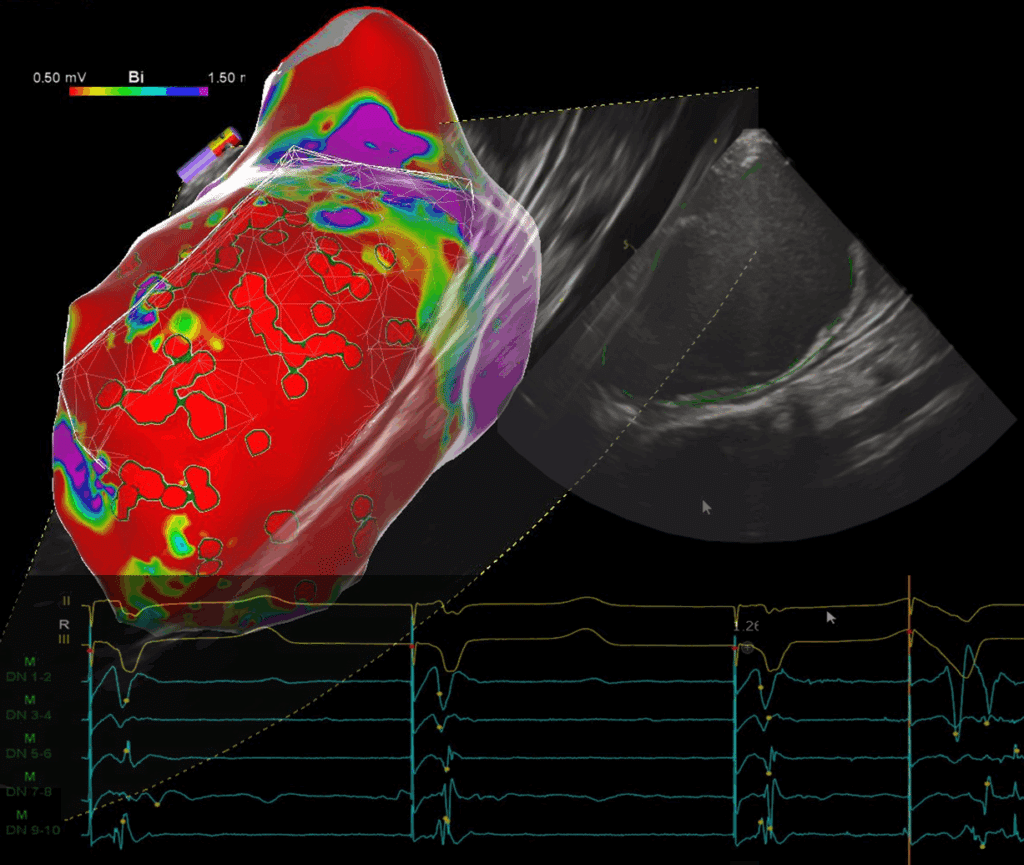

Scar VT

In-depth study of VT mapping techniques and ablation strategies, beginning with fundamental principles of VT re-entry and circuitry, and then expanding into...